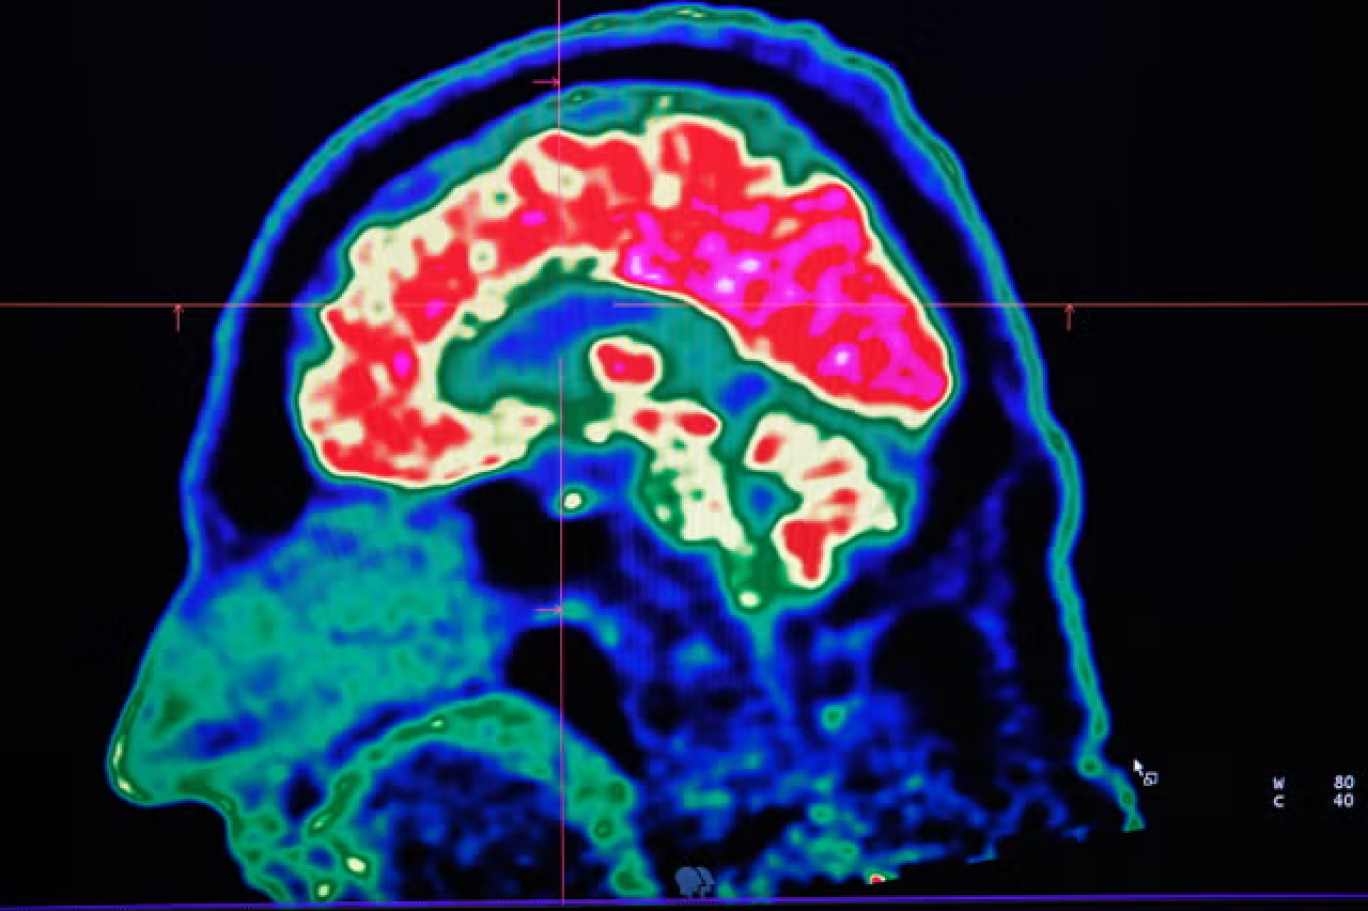

صورة لدماغ بشري تم التقاطها بواسطة ماسح التصوير المقطعي بالإصدار البوزيتروني في مستشفى بريست الاقليمي والجامعي (غيتي)